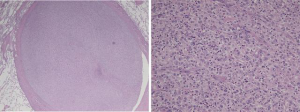

The histopathological features of the tumor were those of a pleomorphic malignancy comprising spindled and epithelioid cells admixed with inflammatory cells (Figure 4). Areas of necrosis and mitoses were sporadically observed. There was no local invasion of the tumor cells outside the vessel wall. These findings were consistent with a diagnosis of PA intimal sarcoma.